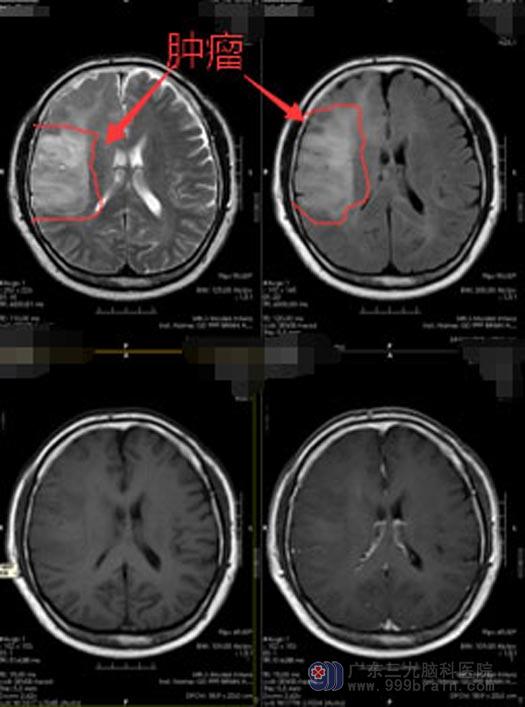

进一步的脑部核磁共振检查发现:右侧额颞岛顶叶、右侧基底节区、双侧丘脑、胼胝体、左侧额顶叶弥漫性病变,考虑为肿瘤性病变,弥漫性星形细胞瘤可能,局部不除外有间变可能。